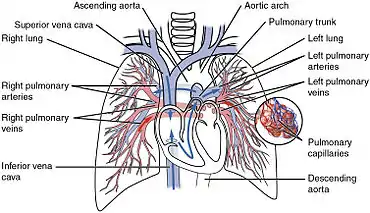

Pulmonary circulation

The pulmonary circulation is the part of the circulatory system in which oxygen-depleted blood is pumped away from the heart, via the pulmonary artery, to the lungs and returned, oxygenated, to the heart via the pulmonary vein.

Oxygen-deprived blood from the superior and inferior vena cava enters the right atrium of the heart and flows through the tricuspid valve (right atrioventricular valve) into the right ventricle, from which it is then pumped through the pulmonary semilunar valve into the pulmonary artery to the lungs. Gas exchange occurs in the lungs, whereby CO2 is released from the blood, and oxygen is absorbed. The pulmonary vein returns the now oxygen-rich blood to the left atrium.[10]

A separate circuit from the systemic circulation, the bronchial circulation supplies blood to the tissue of the larger airways of the lung.